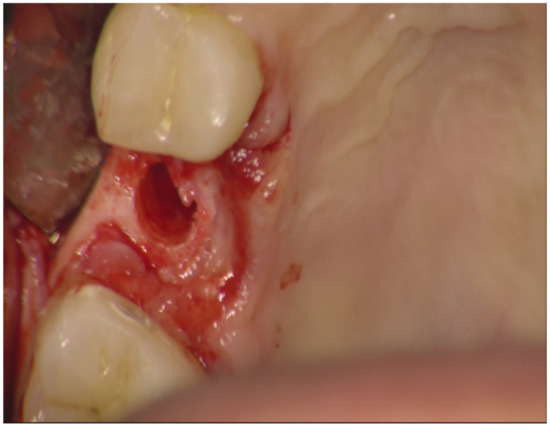

Implant Placement Following Crestal Sinus Lift with Sequential Drills and Osteotomes: Five Years after Final Loading Results from a Retrospective Study

2. Materials and Methods